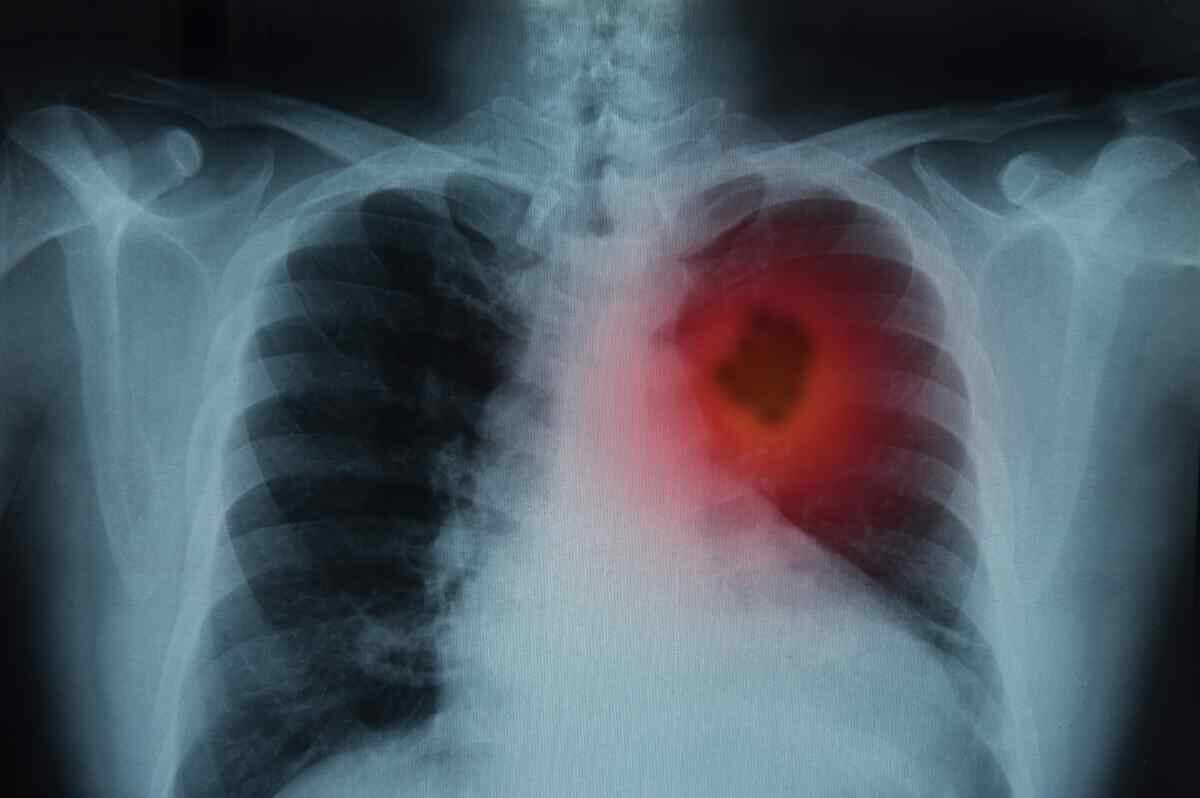

Akciğer kanserinin erken evrede tespit edilebilmesi için, her belirtinin ayrıntılı değerlendirilmesi ve ihmal edilmeden bir uzmana danışılması gerekiyor. Akciğer kanserinin ilk belirtilerinden biri şiddetli, değişik renkte balgamlı öksürük.

NE ZAMAN UZMANA DANIŞMAK GEREKİR? Birkaç haftadır devam eden şiddetli öksürük varsa Öksürürken değişik renkte balgam geliyorsa Sabahları ağzınızda pas tadı varsa ve balgamın da rengi pas rengiyse

Hemoptizi olarak adlandırılan ve akciğer kanserinin en sık görülen semptomlarından biri olan kan tükürmek, akciğer kanserine işaret ediyor.

Amerikan Kanser Derneği tarafından yapılan açıklamaya göre; kan tükürmek akciğer kanserinin erken belirtileri arasında yer alıyor ve ihmal edilmeden uzmana danışmak gerekiyor. NHS (National Health Servic), akciğer kanseri belirtilerini şöyle sıralıyor;